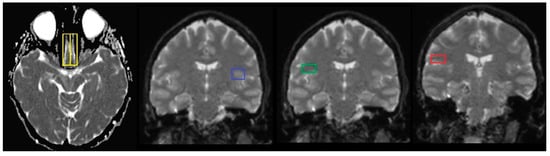

DW images and their automatically generated ADC maps were transferred to a dedicated workstation for analysis. ADC values were obtained through post-processing by manually defining regions of interest (ROIs) on the ADC maps within the targeted tissue. Initially, ROIs were outlined on T2-weighted images (b = 0), where anatomical structures were more easily distinguishable. Next, these ROIs were then transferred onto the corresponding ADC images. For each ROI, measurements included the surface area and the minimum, maximum, mean, and standard deviation of the ADC values. ROI analysis was conducted using imaging analysis software (SyngoVia Plaza version VB10A, Siemens Medical Systems, Erlanger, Germany). The software enabled precise ROI placement as single-point measurements (circular in shape with minimal size), reducing the risk of including adjacent tissue, such as gray matter. In the normal group, ROIs were symmetrically drawn on white matter in both hemispheres. Concerning the COVID-19 category, ROIs were placed specifically within the white matter of the olfactory bulb and taste-related brain regions, including the insular cortex, frontal operculum and parietal operculum (Figure 2).

Figure 2. ROIs in the following areas: olfactory bulbs, insular cortex, frontal operculum, and parietal operculum for the normal cohort (1st row), those in the acute stage of 2020 variant (2nd row), individuals 1 month after infection (3rd row), individuals 36 months after infection (4th row), those in the acute stage of 2024 variant (5th row), and individuals 1 month post-infection (6th row).